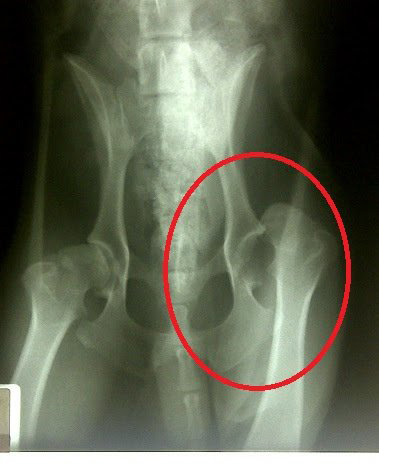

【脱臼】

関節を構成している骨同士が正常な場所からずれてしまう状態のことをいいます。

高齢犬・老犬に多いのが大腿骨の付け根部分に起こる股関節の脱臼とひざのお皿がずれておこる膝蓋骨の脱臼です。

急に足を引きずったり、足をあげたりして歩くようになります。痛みのある様子も見せます。いつもと様子がおかしいと思ったら獣医師に相談することをおすすめします。

そのまま放置していると脱臼から骨折に発展することもありますから。